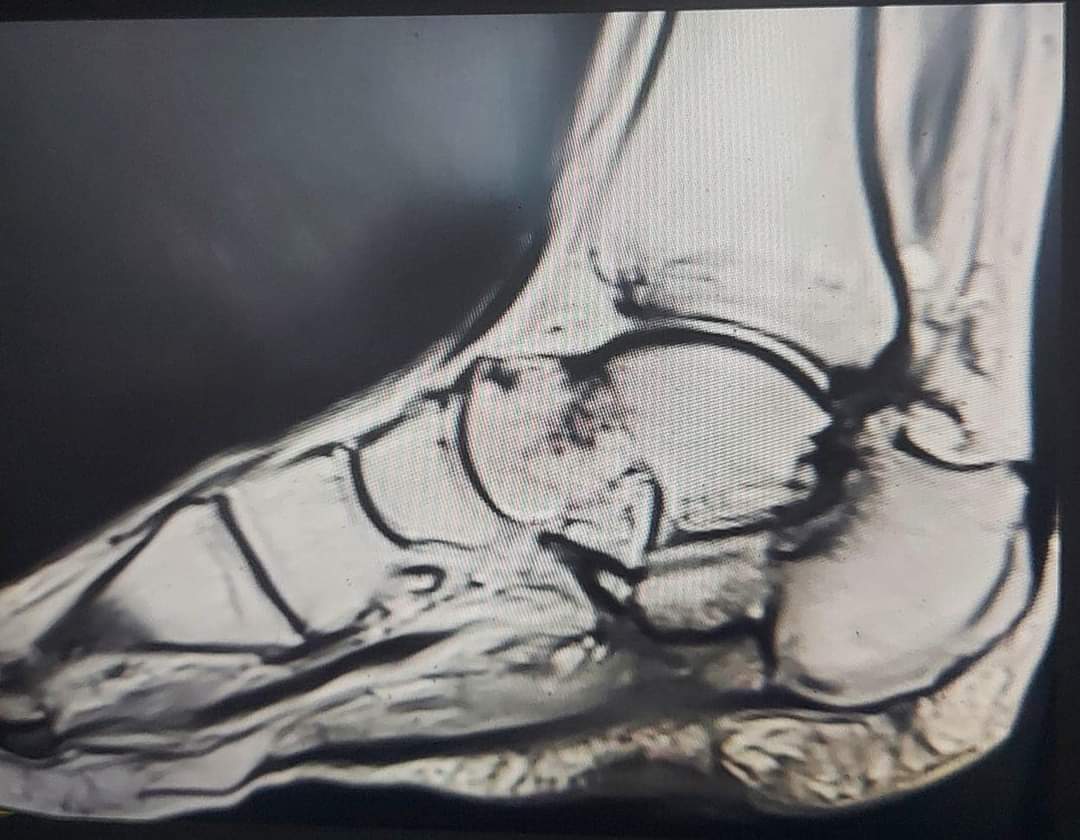

أجرى فريق طبي متخصص من دائرة العظام برئاسة أخصائي أول جراحة العظام المقدم الطبيب بسام الحراحشة عملية نوعية وهي الأولى من نوعها على مستوى المملكة تم فيها ترميم قدم فتاة تبلغ من العمر ١٩ عام بعد إصابتها بإلتهاب مستعصي في عظام القدم والكاحل بعد استنفاذ كل الطرق التقليدية في علاجها .

وقال المقدم الطبيب الحراحشة ان الفتاة راجعت عيادة العظام وعند التشخيص تبين وجود إلتهاب شديد في عظام الكعب والكاحل ،فتقرر بعد ذلك تحويل الفتاة إلى عيادة ترميم الأطراف لعلاجها بطريقه مبتكرة دون الحاجة إلى بتر القدم .

وبين المقدم الطبيب الحراحشة ان العملية اجريت على مرحلتين الأولى تم خلالها استئصال الأجزاء المصابة والمرحلة الثانية تم ترميم عظام القدم والكاحل عن طريق عظام الساق السليمة وتحويل جزء من عظام الساق لتحل مكان الجزء المستأصل من القدم مع إعادة تشكيلها بشكل ينسجم مع شكل القدم ويستطيع المشي عليها.